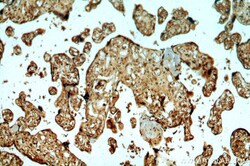

- Immunohistochemistry of paraffin-embedded human placenta using 14412-1-AP (PEG10 antibody) at dilution of 1:100 (under 10x lens).

- Submitted by